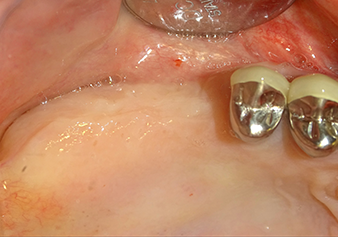

Lo strumento I2A (diametro 2,0 mm) è stato quindi impiegato per perforare il pavimento sinusale in modo graduale e su superfici molto ridotte. Tale metodo piezochirurgico previene il danneggiamento della membrana di Schneider. Durante l'utilizzo di Z25P, la membrana risultava già essere leggermente sollevata dal fluido di raffreddamento fornito attraverso la punta dello strumento (Fig. 3). La quantità di fluido di raffreddamento presente era solo del 50% per evitare che la sede dell'impianto registrasse un'elevata pressione.